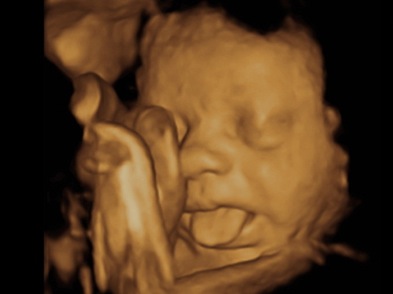

Heavenly 3d4d Ultrasounds 61 Photos 103 Reviews Ultrasound